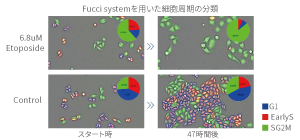

Unbiased phenotype evaluation via AI

Image Credit: Yokogawa Life Science

Machine learning also enables the bias-free digitization of visually rated trials. Users can enable automatic recognition by simply selecting the shape they wish the software to learn.